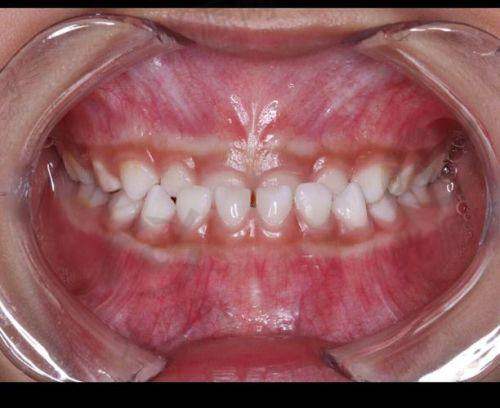

下兜齿一般都是骨性的吗?

首先,答案是肯定的,下兜齿一般都是骨性的。下颌骨的结构性异常通常是地包天的根本原因,尤其是在儿童和青少年时期,颌骨的发育不均衡会导致这种情况的发生。根据临床数据,约有35%的地包天患者是属于明确的骨性畸形类型,而其余的则可能是由于牙齿位置的问题造成的。

这种骨性地包天通常在儿童时期就已经开始显现,更常见的是由于遗传因素造成的,如父母有类似情况,孩子的发病率会显著上升。此外,习惯性口腔行为,比如长时间吮指、舌头推挤上牙、呼吸口呼吸等也可能在一定程度上促成下颌的过度生长。